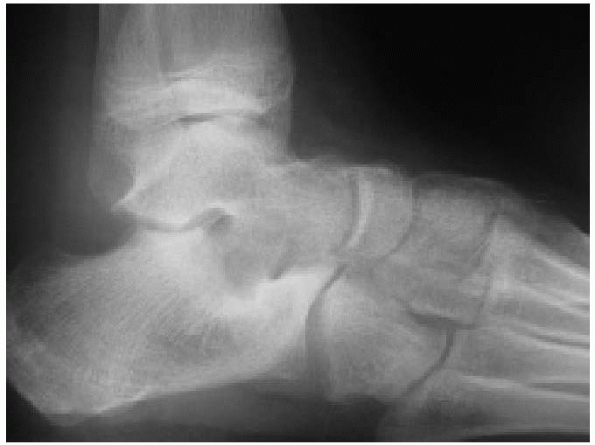

are posteroanterior, lateral, and axial views. The posteroanterior view

shows the calcaneocuboid and talonavicular joints well. The lateral

view is excellent at showing the congruity of the posterior articular

facet and allows calculation of Böhler’s angle (see Fig. 27-9).

The axial view demonstrates the tuberosity, the body, the sustenaculum

tali, and the posterior facet of the calcaneus.. Oblique views are also

useful and will show a fracture of the anterior process more clearly (Fig. 27-14).136

angle. This is the angle between a line drawn from the highest point of

the anterior process to the highest point of the posterior facet and a

line drawn tangential to the highest point of the calcaneal tuberosity.

The normal value in an adult is between 20 and 40 degrees. In a child,

the angle is slightly less than in an adult and may be due to the

incomplete ossification of the calcaneus. It is advisable to perform a

lateral radiograph of the contralateral calcaneus to use as a

comparison rather than accept the absolute value of Böhler’s angle. The

child’s calcaneus does not resemble that of an adult until after 10

years of age.67,69,118,166

Another angle which is not so easy to measure is “the crucial angle of

Gissane”. This is the angle formed by two strong cortical struts seen

on the lateral radiograph. One runs along the lateral margin of the

posterior facet and the other runs up to the anterior process of the

calcaneus. The angle between them ranges from 95 to 105 degrees (see Fig. 27-9).47